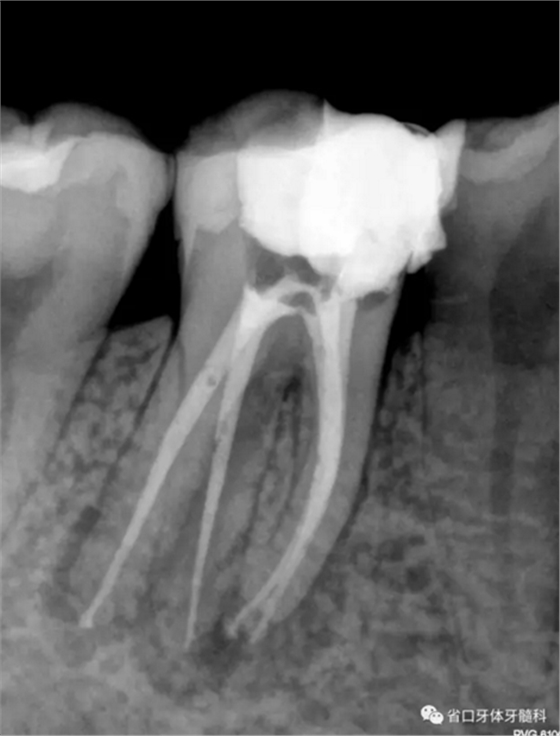

圖2 術后根充片

術后隨訪x線片,遠頰、遠舌根尖低密度影消失,近頰根尖低密度影局限(提示近頰根尖瘢痕愈合),嵌體不阻射x線。